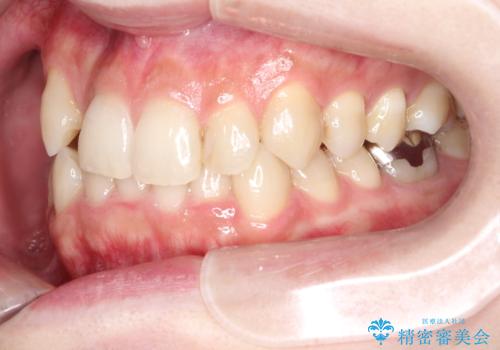

- 八重歯を治したいとのことで来院されました。

右上の犬歯が外側に飛び出して、二番目の歯が内側に入っている状態でした。

上の奥歯を後方に移動させてスペースを確保して、前歯のガタガタを改善する計画としました。